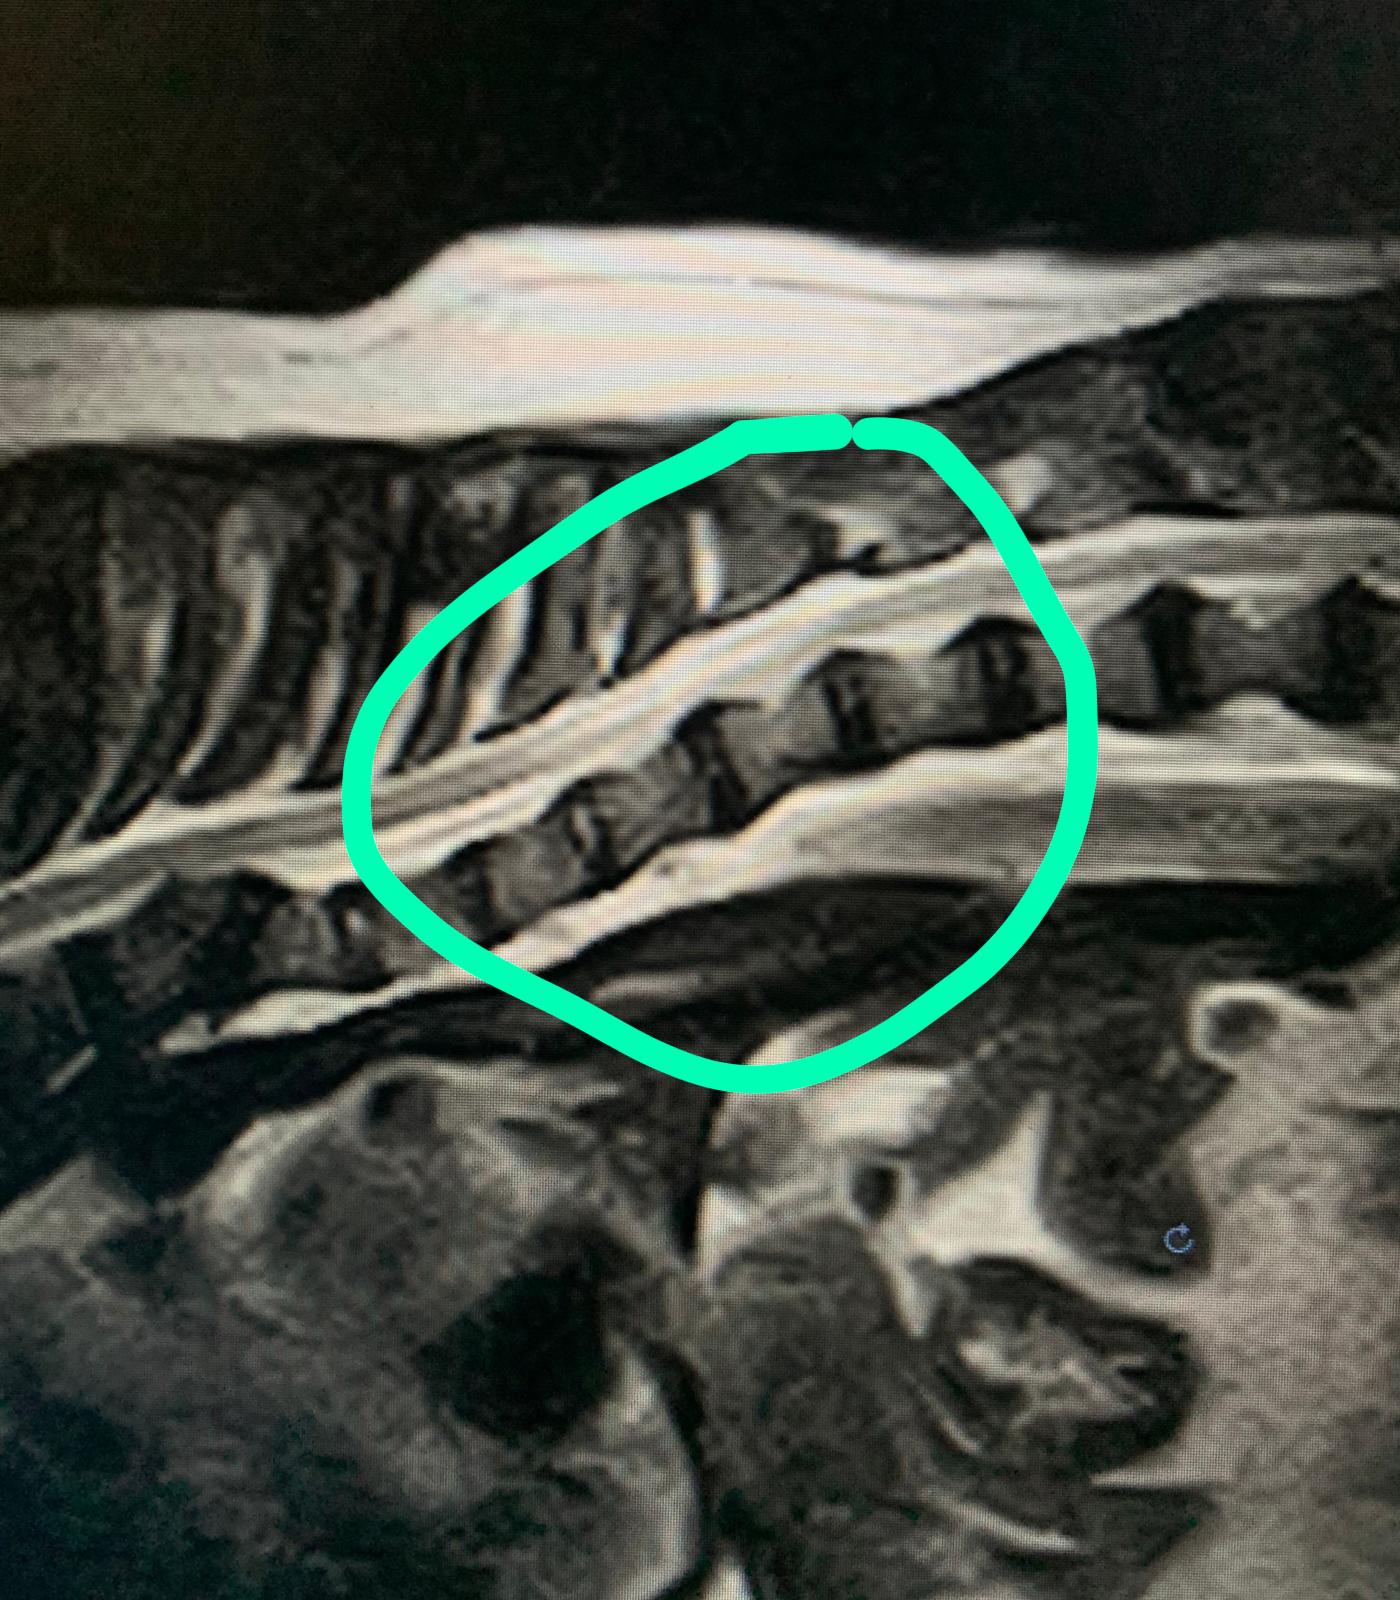

“Ci siamo accorti – spiega – che il cane presentava una anomalia molto rara del midollo spinale chiamata cisti sub aracnoidea. Se fosse degradata avrebbe portato alla paralisi delle zampe posteriori. Una situazione delicata“.

“Fondamentale è la risonanza magnetica che ci ha permesso di individuare esattamente l’anomalia. Senza questo esame strumentale non avremmo potuto averne una certezza scientifica così precisa. Non solo, questa ci ha permesso di valutare in modo preciso lo stato del midollo per capire se il cane fosse operabile o meno. Fortunatamente l’intervento è stato possibile andando a correggere l’anomalia e regalando a Mailo un nuovo futuro“.